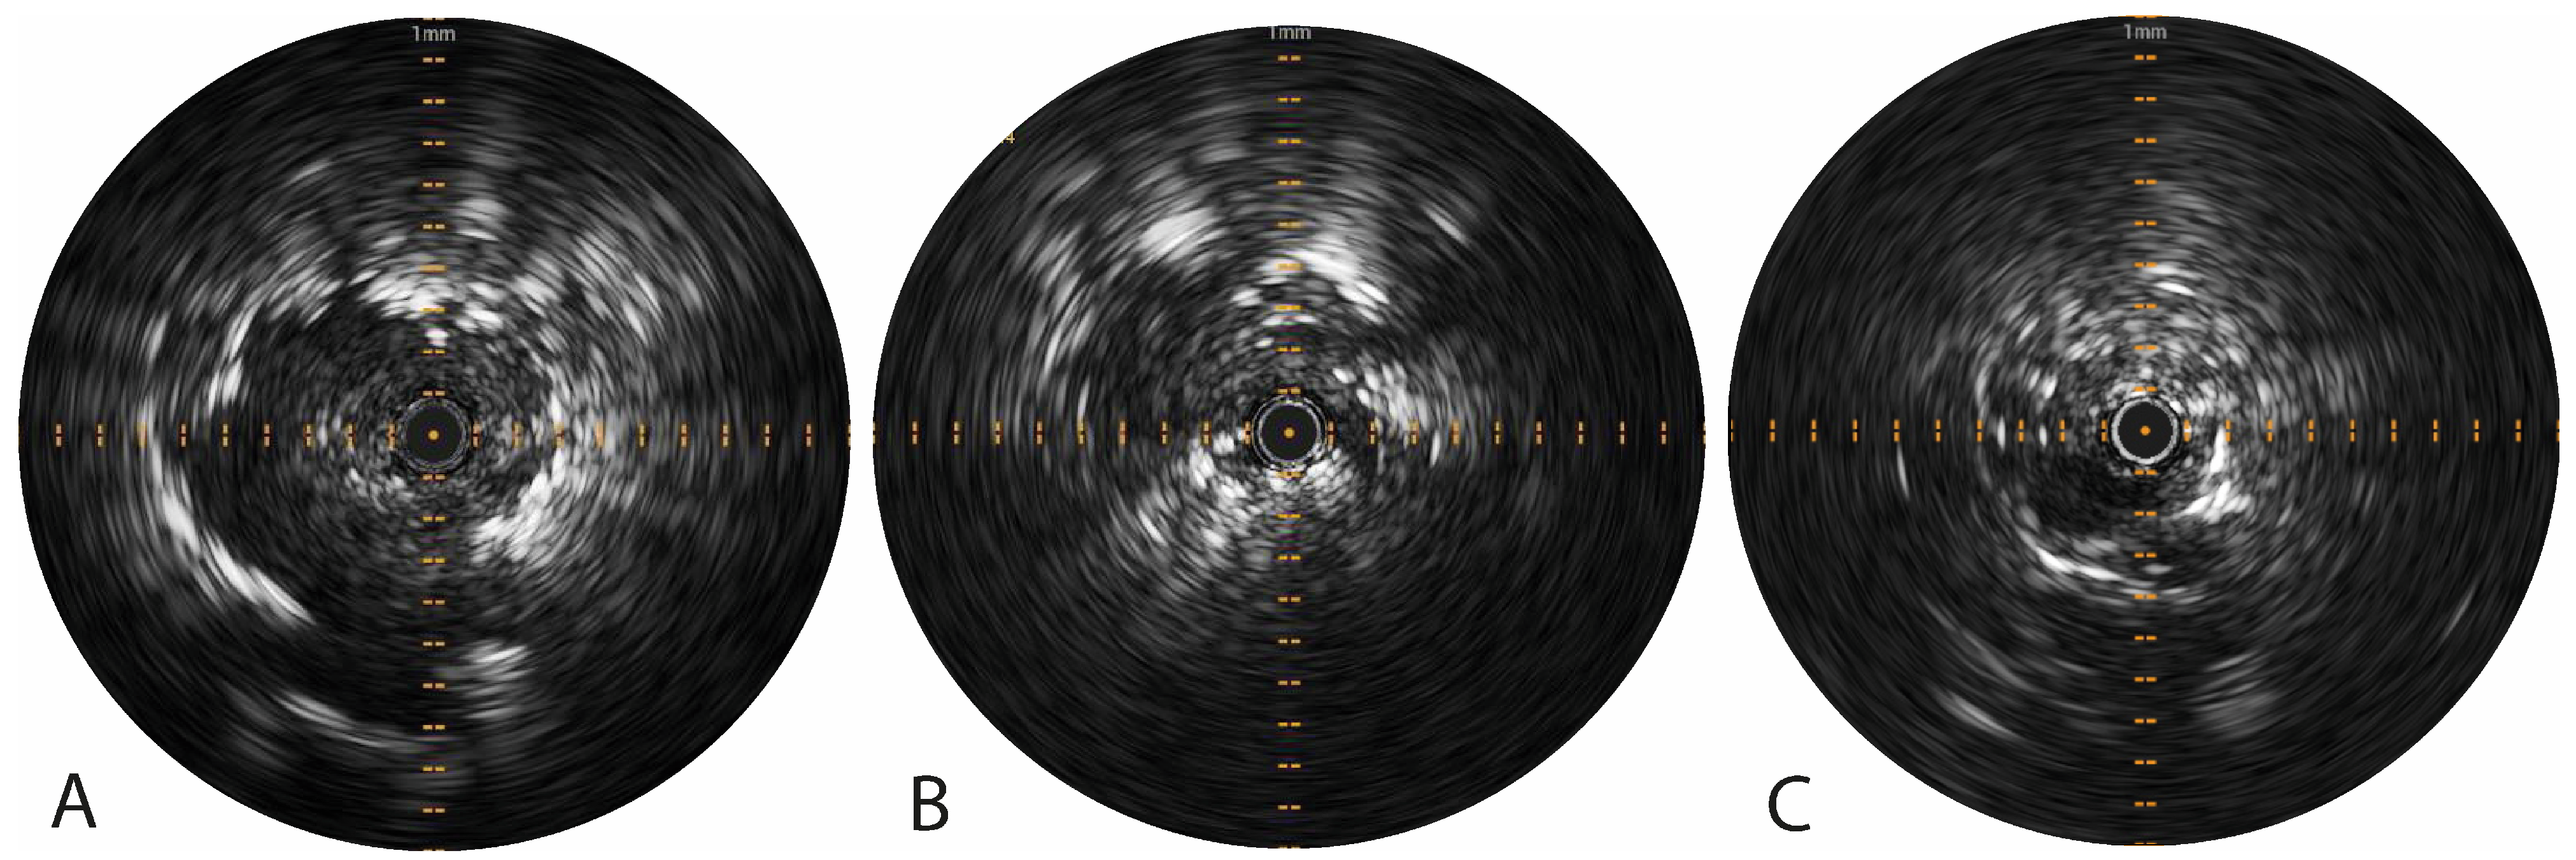

2.3.1. Pioneer Plus Radial Ultrasound

3.1. Pioneer Plus Radial Ultrasound

| Tumor visibility on radial US imaging, n (%) | 29 (96.7%) | ||

| Real-time radial US visibility of tracer injection, n (%) | 0 (0.0%) | ||